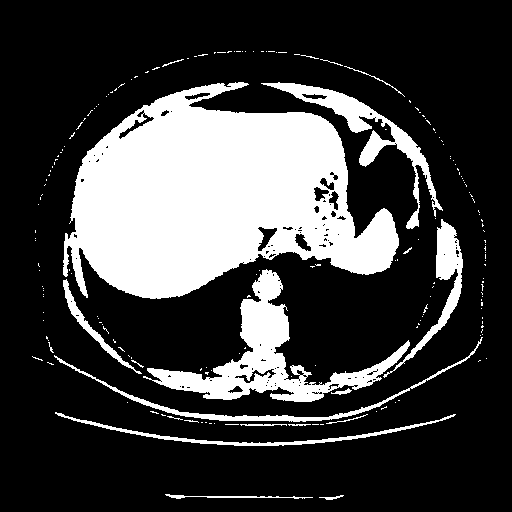

Original NATIVE CT scan (input)

Full window (WL 1023.5, WW 4095 β†’ Low βˆ’1024, High +3071)

Actual HU range: [-1024.0, 3071.0]